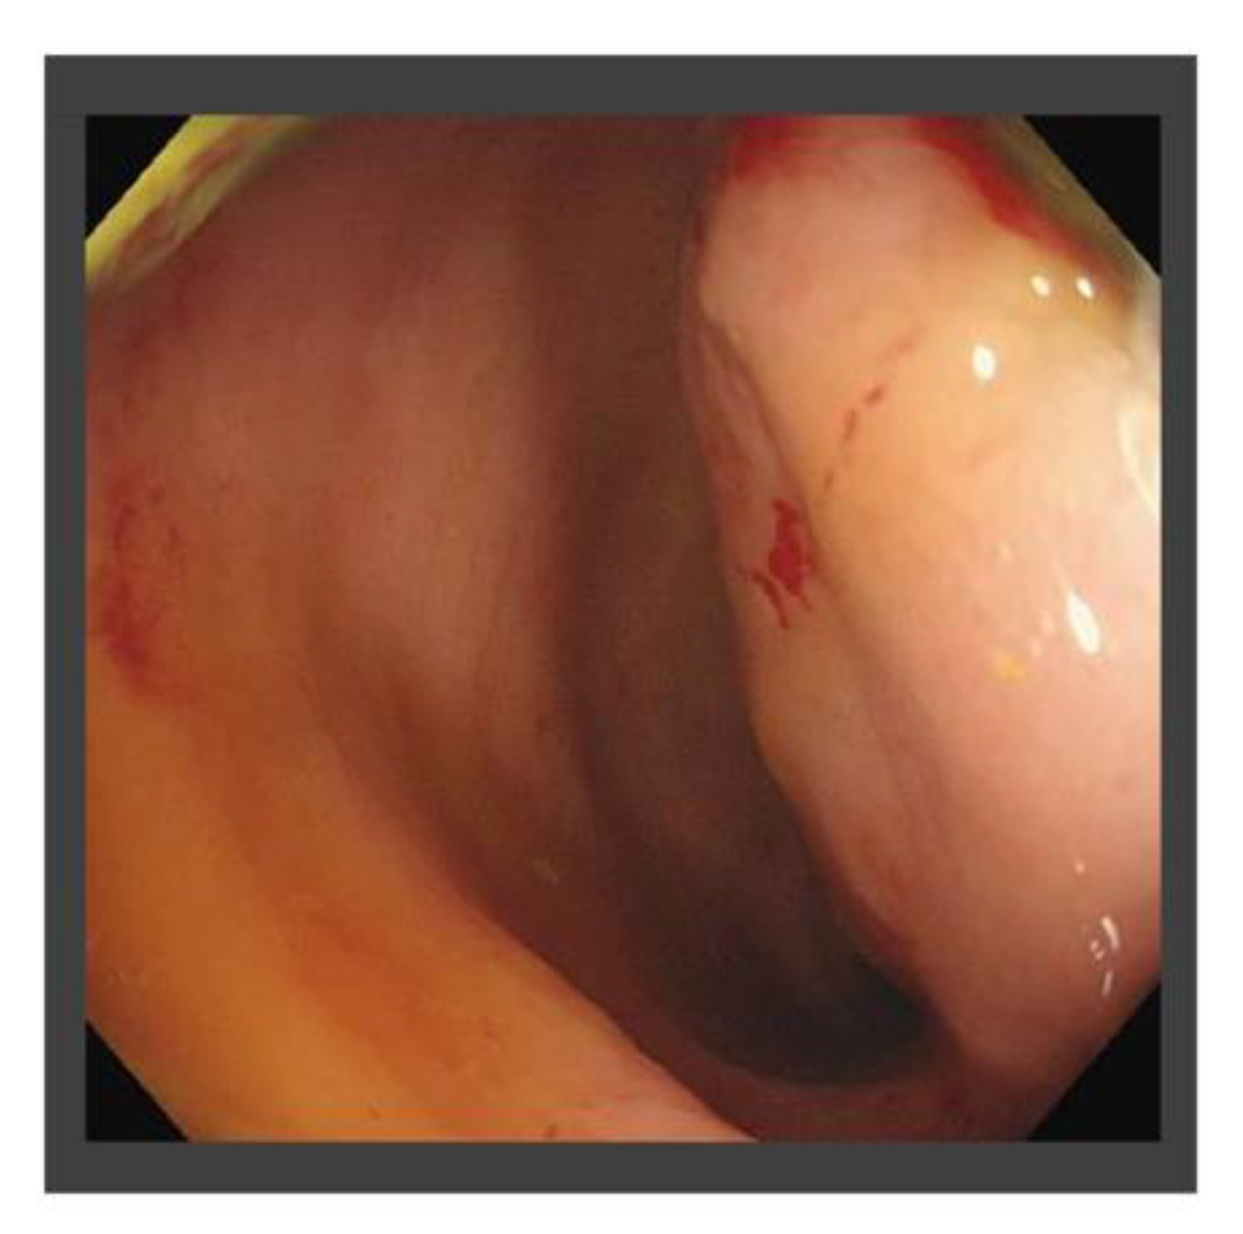

| X | May | The histological diagnosis of pelvic metastasis of HCC |